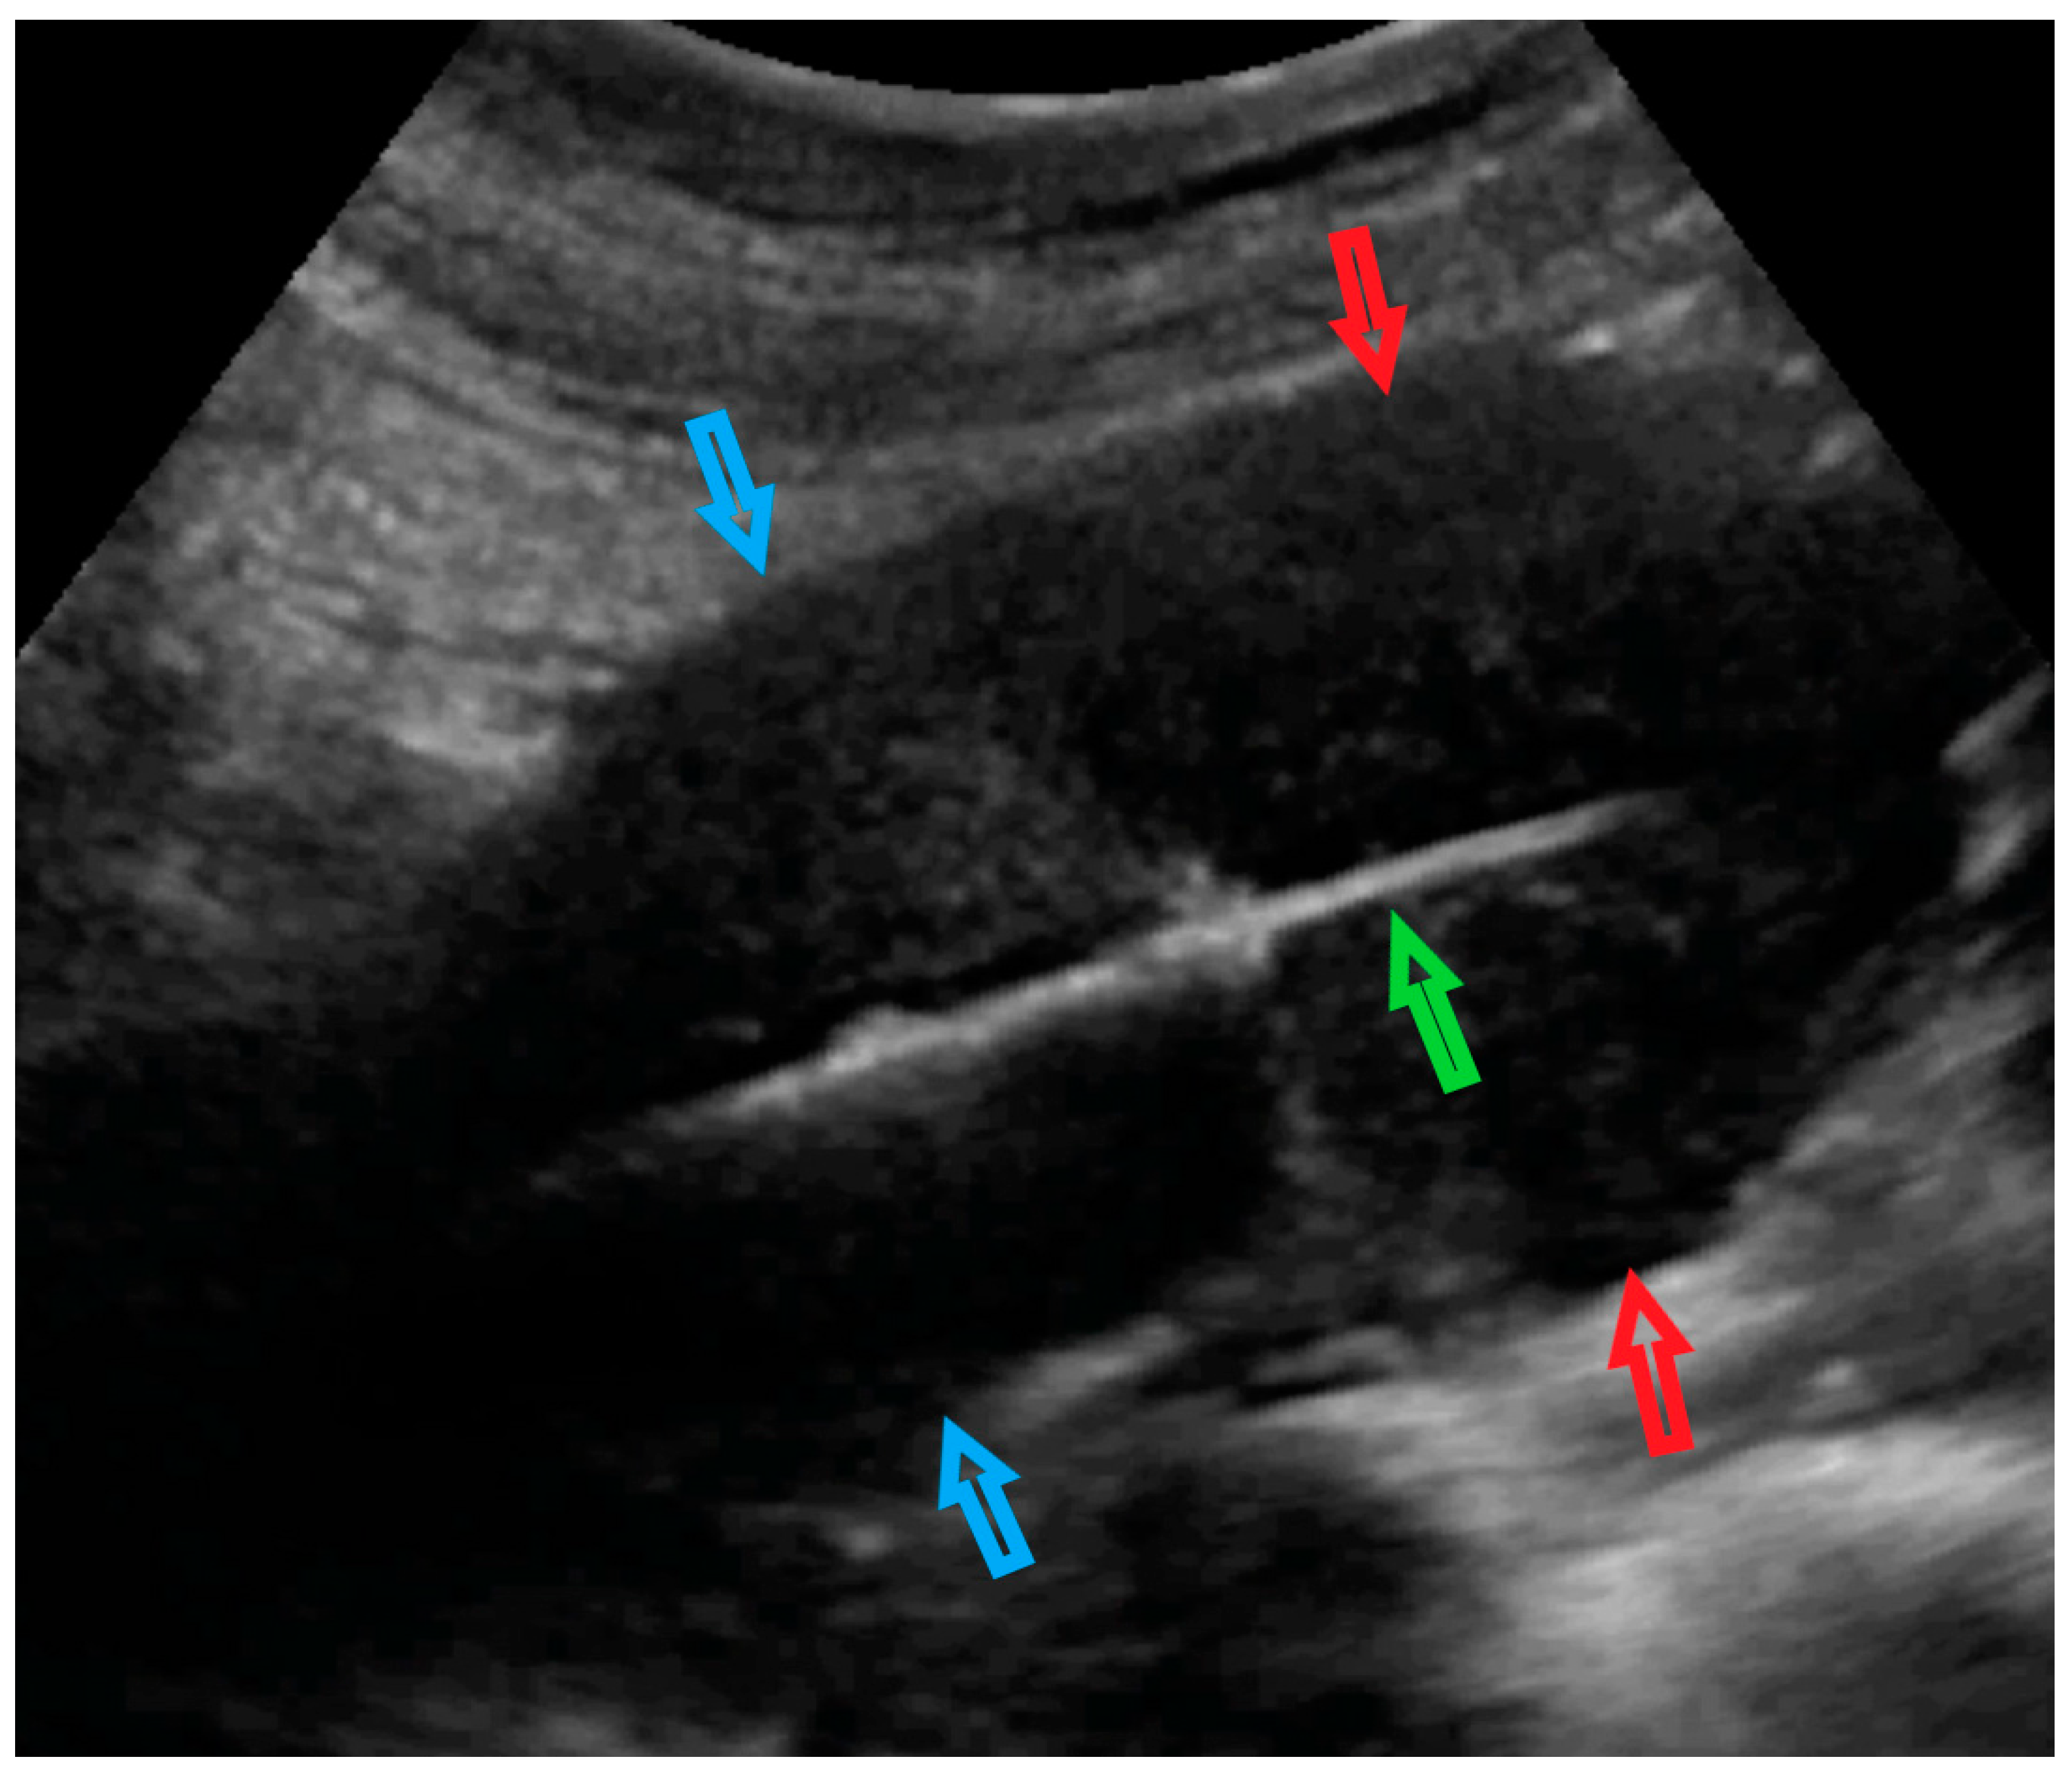

| 1 (44) | Typical uterine lesion (myoma) | Figure A1 | No | Yes | Leiomyoma, cellular variant (UG-TUC core needle biopsy) | Yes (lesion enlarged during follow-up) | Leiomyoma, cellular variant | No | Yes |

| 2 (36) | Sarcoma suspicion | Figure A2 | Yes | Tumorectomy, uterus preservation (young age) | LMS (UG-TUC core needle biopsy) | Yes | LMS | No | Yes |

| 3 (37) | Atypical uterine lesion | Figure A3 | Yes | No | Lipoleiomyoma (UG-TUC core needle biopsy) | No | - | Yes | Yes |

| 4 (56) | Atypical uterine lesion | Figure A4 | Yes | Yes | Leiomyoma (transvaginal ultrasound guided core needle biopsy) | Yes | Leiomyoma and adenomyosis | Yes | No |

| 5 (50) | Atypical uterine lesion (metastatic adenocarcinoma G3 in inguinal lymph node) | Figure A5 | Yes | No | Leiomyoma (UG-TUC core needle biopsy) | No | Uterus / tumor not resected because primary urological carcinoma was diagnosed | Yes | Yes |

| 6 (38) | Atypical uterine lesion | Figure A6 | Yes | No | Leiomyoma, epithelioid variant (UG-TUC core needle biopsy) | Yes (lesion enlarged during follow-up) | Leiomyoma, epithelioid variant | Yes | Yes |

| 7 (29) | Atypical uterine lesion | Figure A7 | Yes | Yes | Leiomyoma (UG-TUC core needle biopsy) | Yes | Leiomyoma with signs of degenerations | Yes | Yes |

| 8 (52) | Atypical uterine lesion | Figure A8 | Yes | Yes | Total abdominal hysterectomy performed without core need biopsy, because of patients age and lesion ultrasound pattern recognition. Note: frozen section result: leiomyoma | Yes | STUMP | - | - |